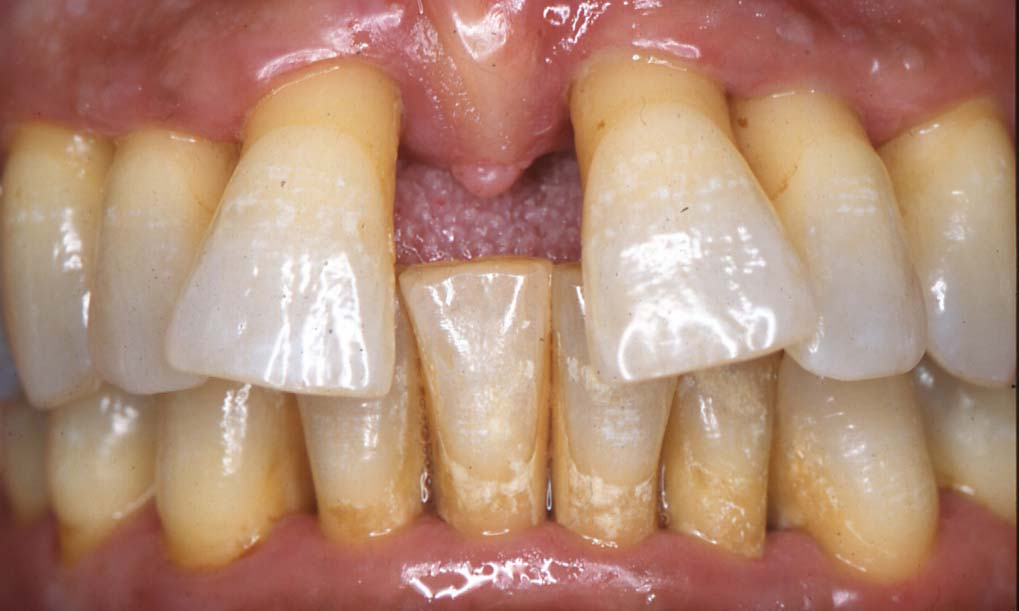

ΠΕΡΙΟΔΟΝΤΙΤΙΔΑ

ΜΙΑ ΠΑΘΗΣΗ ΑΝΑΣΤΡΕΨΙΜΗ;

Η περιοδοντίτιδα αποτελεί την κύρια αιτία απώλειας των δοντιών στους ενήλικες. Έχει συνήθως χρόνια πορεία που πολλές φορές περνά απαρατήρητη και η διάγνωση γίνεται όταν η νόσος έχει εξελιχθεί αρκετά.

Είναι απαραίτητος λοιπόν ο τακτικός έλεγχος με σκοπό την έγκαιρη διάγνωση των περιοδοντικών προβλημάτων. Στο 80% των περιοδοντιτίδων η νόσος θεωρείται θεραπεύσιμη και μερικές φορές μέχρι έναν βαθμό αναστρέψιμη.  Ένα ποσοστό περίπου 20% ανήκουν σε κατηγορίες περιοδοντίτιδας οι οποίες παρουσιάζουν χαρακτηριστικά γνωρίσματα επιθετικής και ταχείας εξέλιξης νόσου. Στις περιπτώσεις αυτές η προβλεψιμότητα της θεραπείας ελαττώνεται σημαντικά. Όπως για όλα τα νοσήματα, και για τα νοσήματα του περιοδοντίου σημαντικό ρόλο παίζει η πρόληψη. Η περιοδοντική νόσος μπορεί να προληφθεί αλλά και να αντιμετωπισθεί προσφέροντας στον ασθενή τη δυνατότητα να διατηρήσει τη φυσική του οδοντοφυία για μεγάλο χρονικό διάστημα. Ένας μεγάλος περιοδοντολόγος , ο Schlóger, έλεγε: «Απαιτούνται τα μικρόβια για να εκδηλωθεί η περιοδοντική νόσος, αλλά χρειάζεται ένας απληροφόρητος οδοντίατρος και ένας αδιάφορος ασθενής για να απολεσθεί η φυσική οδοντοφυία».

ΤΑ ΣΥΜΠΤΩΜΑΤΑ ΤΗΣ ΠΕΡΙΟΔΟΝΤΙΤΙΔΑΣ

Η περιοδοντίτιδα εκδηλώνεται με διάφορα συμπτώματα τα οποία δε συνυπάρχουν απαραίτητα όλα στον ίδιο ασθενή και η έντασή τους δε συμβαδίζει πάντα με τη σοβαρότητα της νόσου.

Τα κυριότερα συμπτώματα της περιοδοντίτιδας

είναι τα εξής:

• Αιμορραγία των ούλων κατά το βούρτσισμα ή αυτόματα

• Κόκκινα και διογκωμένα ούλα.

• Ούλα που έχουν αποκολληθεί από το δόντι ή έχουν υποχωρήσει

• Κινητικότητα δοντιών

• Αλλαγή στη θέση των δοντιών

• Κακοσμία